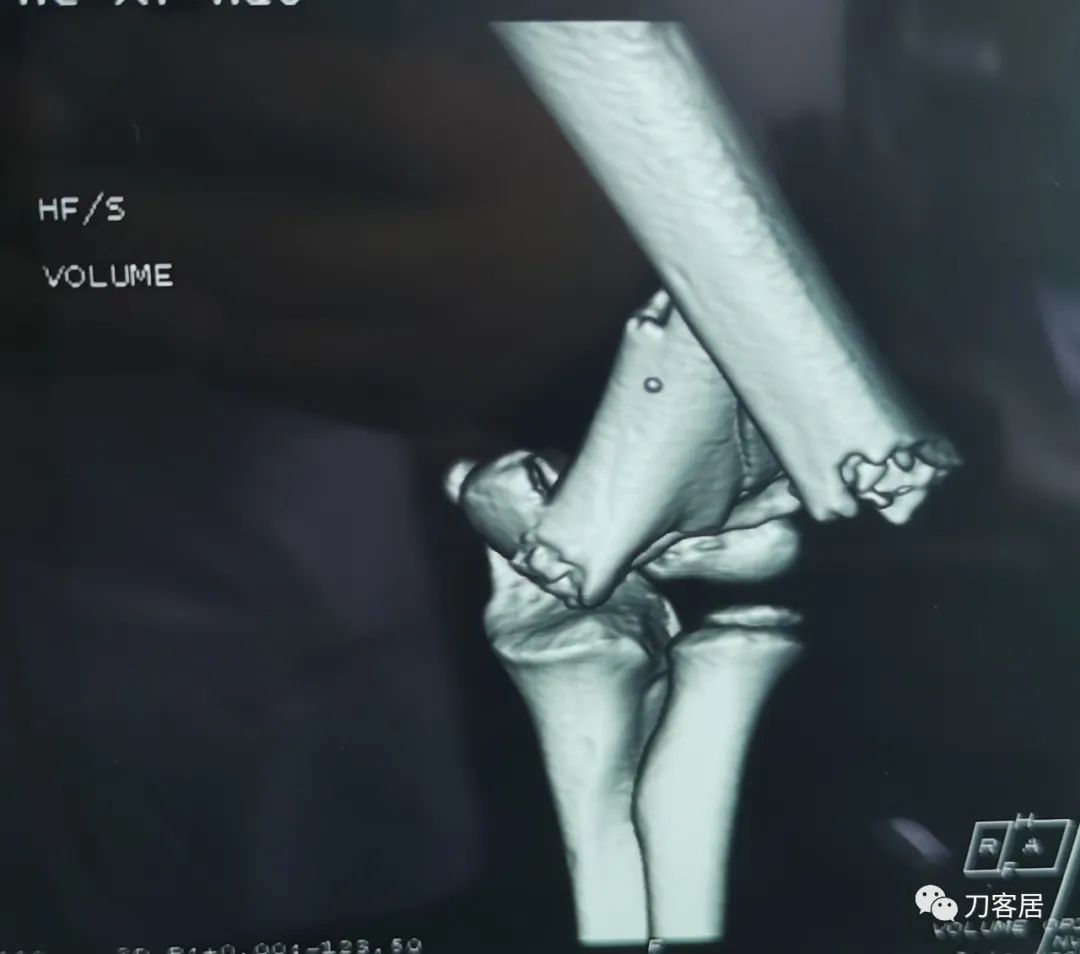

查体:左侧肘关节肿胀明显、疼痛、畸形,局部可见明显青紫瘀斑,左肘关节活动受限,肱骨远端环形压痛(+),局部可及异常活动及骨擦感形成,左上肢末梢桡动脉可触及,左侧腕关节及拇指背伸活动受限,左侧虎口区感觉麻木。辅助检查:自带X线及CT片示:左肱骨髁间粉碎性骨折。

入院诊断:1. 左肱骨髁间粉碎性骨折;2.左肱骨远端骨骺损伤;3. 左桡神经损伤。

20210922当地省中医院三维CT01